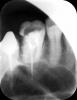

mur-in-law Опубликовано 17 декабря, 2012 Автор Поделиться Опубликовано 17 декабря, 2012 1. первичный диагноз по этим зубам2. протокол эндодонтической обработки 6 и 7зубов3. все ли каналы найдены и пройдены?4. пломбировочный материал (гутаперча? силер?) для каналов и методика пломбировки5. качество пломбировки каналов (контрольный снимок)6. Название временной пломбы и срок ее ношения до фиксации ВКВ7. конфигурация ВКВ (количество, длина и диаметр внутриканальных элементов, остаточные объемы тканей корня и т.д.)8. цемент, на который фиксировалась ВКВ и толщина цементной пленки (у Вас, похоже, не пленки, а прокладки)Спасибо! Отвечу по Вашим пунктам.1. Это не могу сказать, что-то типа сколы, кариес, дефект пломбы.2. Протокол? Напишу что делали.В семерке корнями не занимались, они уже были запломбированы ранее. Просто поставили ВКВ. В шестерке были обработаны каналы (после экстирпации), затем положен Крезофен в два канала. Всего в шестерке три канала было найдено и обработано. Это первого февраля было сделано. Затем 17 февраля были пломбированы каналы эндометазоном и гуттаперчивыми штифтами. Всего на три канала было использовано девять штифтов. Затем была припасовка и фиксация анкерного штифта за 380 рублей, филтек XT с применением дайректа жидкого. Вот снимки.3. Уже ответил (во втором пункте).4. Уже ответил во втором пункте.5. Снимок выложил.6. Временной коронки не было. Была временная пломба. Название не знаю. Срок ношения до фиксации ВКВ - с 13 января до 1 февраля, примерно 17 дней.7. Вкладка цельнолитая с двумя корневыми штифтами. 8. Цемент стеклоиономерный. Ссылка на комментарий

DmitrySH Опубликовано 17 декабря, 2012 Поделиться Опубликовано 17 декабря, 2012 Смотрю давнишнюю тему подняли. Давайте обсудим( самое основное). 1. 7 зуб. Не осуществлено адекватное эндодонтическое лечение. передне-щечный канал не запломбирован. в заднем похоже половина канала пустая, по снимку немогу понять точнее.2. Лечение 6 зуба было проведено без изоляции от полости рта (коффердама) . 3. 9 штифтов на 3 канала - не серьезно. Да их вообще не считают. 4. С такой полостью как на 6 зубе вкв лучше5. И тп и тд . прогноз неоднозначный и там и там. Ссылка на комментарий